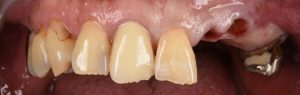

大きな虫歯と根の破折で抜歯適応となった歯を複数本インプラントで再建した症例

初診時。複数本のブリッジがグラついて食べ物が噛めないとのことでご来院されました。レントゲン写真で精査すると、土台に大きな虫歯ができて、一部脱離していることがわかりました。ブリッジを外してみると、そこに…